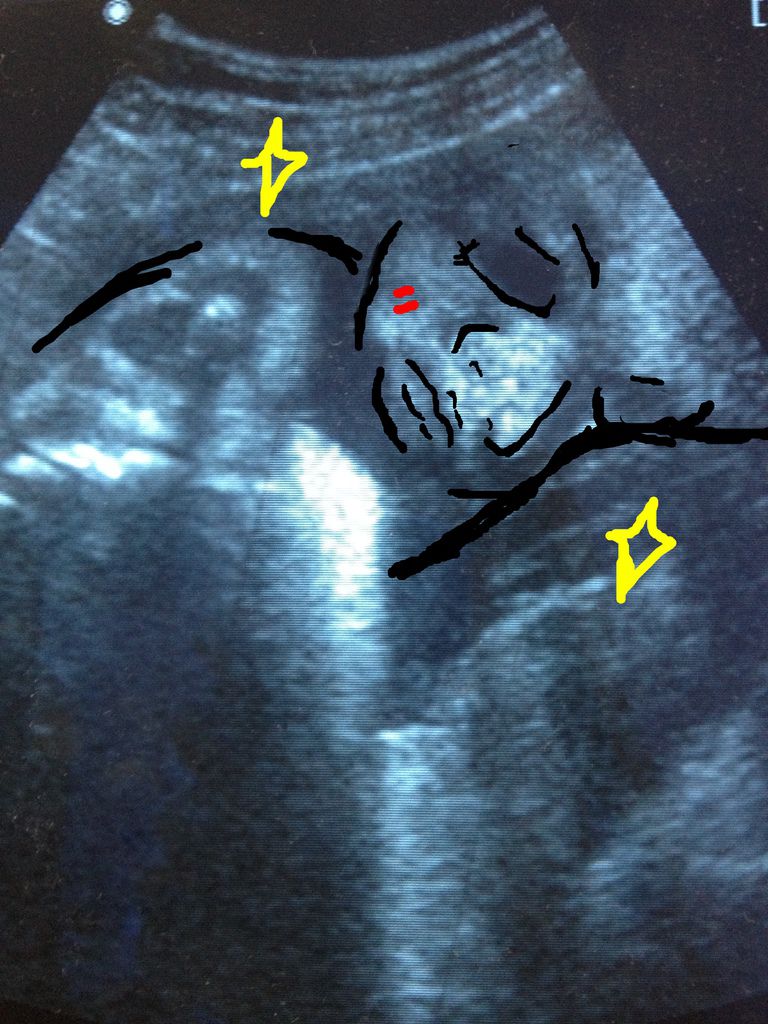

(8個月的肚肚嚕)

(剛好是肚肚睡覺的臉臉 ,真可愛♥)

照超音波的時候,因為榮總都不會幫你印照片(陳醫師解釋:「不環保」,嗯....我認同哈哈。)

所以偷偷翻拍了一張♥

這張跟他爸爸睡覺的臉也真的是一模一樣耶,我真的覺得太神奇了。

那天產檢的時候我姊妹淘陪我去,我一直在驚呼說啊他的腳腳,或者啊他的鼻子,結果她完全霧煞煞哈哈哈

陳醫師還誇我很會看超音波,說不定我有做婦產科醫生的潛力哎?

不過我還是再回家要把照片上傳到fb前,特地的把五官畫出來

因為孩子的爸每次都看不懂哈哈哈哈哈哈